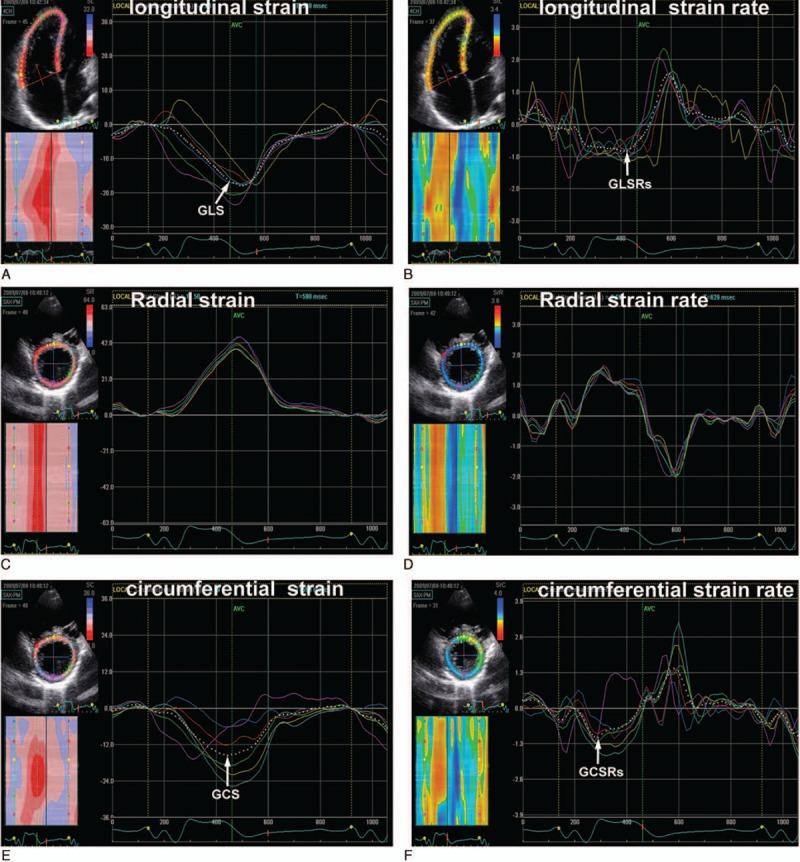

Right ventricular (RV) and left ventricular (LV) dysfunction is an important determinant of poor clinical status in repaired patients with tetralogy of Fallot (TOF). The purpose of our study is to assess the impact of surgical repair on short-term RV and LV function by 2-dimensional speckle tracking echocardiography (STE).Sixty-seven patients (median age 12 months) with TOF before and 6 months after repair and 35 healthy subjects were studied. The patients were divided into the younger (age at surgery ≤12 months) and older (age at surgery >12 months) subgroups. RV and LV global longitudinal systolic strain and strain rate (SR), and LV global circumferential and radial systolic strain and SR were measured by STE. After repair, RV longitudinal strain and SR increased in the younger patients, whereas RV longitudinal SR was decreased in the older patients. LV deformation parameters were unchanged in all patients. In the multivariate analysis, patients with better RV and LV deformation parameters preoperatively were identified to have better RV and LV strain and SR postoperatively (P < 0.05 for all). The surgical approach of the pulmonary valve ring was predictive of RV and LV systolic function postoperatively (P < 0.05 for all).After TOF repair, short-term RV function improvement is identified in the younger but not in the older patients, whereas LV function is unchanged in all patients. The preoperative RV and LV deformational indices are the determinant of postoperative biventricular function improvement. STE appears to be a valuable tool for assessment of biventricular function after congenital heart disease surgery.

研究了67例TOF患者(中位年龄12个月),分别在修复术前和术后6个月,以及35名健康受试者。患者被分为较年轻(手术年龄≤12个月)和较年长(手术年龄>12个月)亚组。通过STE测量RV和LV整体纵向收缩应变和应变率(SR),以及LV整体圆周和径向收缩应变和SR。修复后,较年轻患者的RV纵向应变和SR增加,而较年长患者的RV纵向SR降低。所有患者的LV变形参数均未改变。在多变量分析中,术前RV和LV变形参数较好的患者术后RV和LV应变及SR也较好(所有P<0.05)。肺动脉瓣环的手术方式可预测术后RV和LV收缩功能(所有P<0.05)。